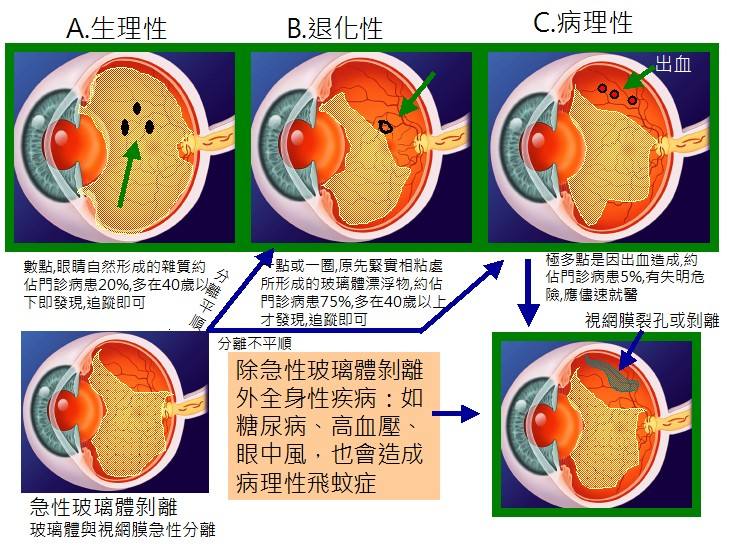

A:飛蚊症是指眼前有飄動的黑影,尤其是看白色背景的時候症狀更加明顯,同時有時候有些人會伴有閃光感,眼前一亮一亮的症狀,引起的原因主要是玻璃體液化和後脫離。絕大多數的飛蚊症都是生理性,但是有大約20%的飛蚊症,可能是病理性,具有威脅視力下降的情……

A:飛蠅症又稱飛蚊症和玻璃體混濁,是指玻璃體內出現不透明體,造成患者視物出現模糊。人出生時玻璃體呈凝膠狀態,是重要的屈光介質,正常的玻璃體隨著年齡逐漸出現液化,從而導致玻璃體混濁。此外,一切玻璃體混濁是由於病理原因所導致,例如玻璃體出血、葡萄……

A:眼前出現飛蚊的症狀往往是因為玻璃體發生了液化、變性和混濁,通常情況下玻璃體的混濁,比較多見於近視眼的人和年歲比較大的中老年人,還要特別重視的一個問題是當眼底有病變發生的時候,也會出現玻璃體的混濁、玻璃體混濁的加重,這時候眼前飛蚊的症狀需要做……

A:得了飛蚊症主要通過以下方法進行治療:1、藥物治療:藥物治療飛蚊症的療效不確切,飛蚊症又稱玻璃體混濁,可以分為生理性的玻璃體混濁和病理性的玻璃體混濁。對於生理性的玻璃體混濁,通常對患者的視力沒有特別的影響,一般不需要進行特殊治療,可以口服卵……

A:年輕人飛蚊症可由以下常見原因所導致:1、高度近視:通常是指600度以上的近視,在近視的發展過程中玻璃體會逐漸液化,從而表現為飛蚊症。如果除了有飛蚊症的感覺,還伴有眼前的異常散光感,或者短時間內飛蚊不斷增加,年輕人需要到醫院進行眼底檢查,防……

A:年輕人眼睛出現飛蚊症,根據病因不同治療也有所不同,常見病因如下:1、高度近視所引起:通常是指600度以上的近視,在近視的發展過程中,玻璃體逐漸液化出現飛蚊症。如果僅有飛蚊症的感覺,通常不需要進行特殊的治療,但是需要去醫院進行定期檢查,防止……

A:眼睛出現飛蚊,可以通過以下方法進行治療並緩解:1、藥物治療:藥物治療飛蚊療效並不確切,眼睛出現飛蚊又稱玻璃體混濁,可以分為生理性的玻璃體混濁和病理性的玻璃體混濁。生理性的飛蚊症,主要是由於隨著年齡的增加,玻璃體逐漸液化所導致,通常對患者的……

A:眼睛裡有飛蚊的現象主要是因為玻璃體發生了液化、變性和混濁,玻璃體原本在眼睛裡邊是一個膠凍狀的結構,由於近視眼以及中高度近視或者年齡過大了,中老年人就會出現玻璃體的液化、變性和混濁,這種情況下很難通過任何治療,將已經液化的玻璃體恢復到膠凍狀的……